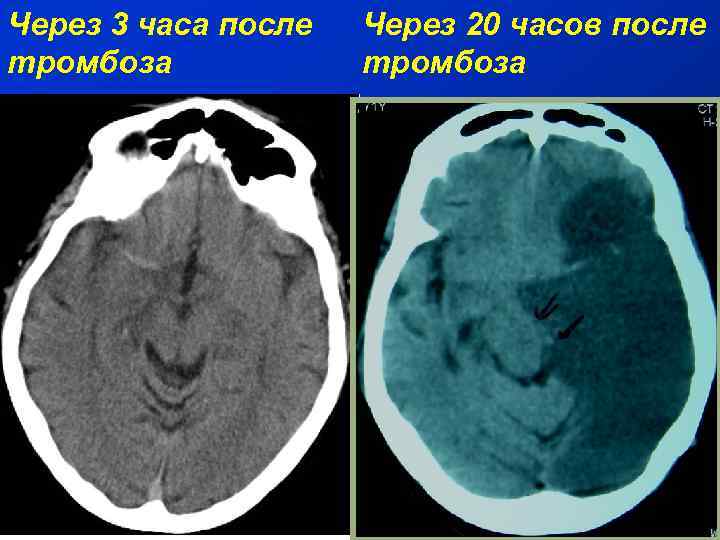

Через 3 часа после тромбоза Через 20 часов после тромбоза

Лечение ишемического инсульта Интенсивная противоотечная и нейропротекторная терапия в условиях специализированного реанимационного отделения с нейромониторингом; • Управляемая гипотермия; • Контроль внутричерепного давления; • Локальный и системный тромболизис; • Декомпрессивная краниотомия; • Эндоваскулярные методы (тромэктомия, баллонная ангиопластика, стентирование); • Эндартерэктомия; • ЭИКМА •